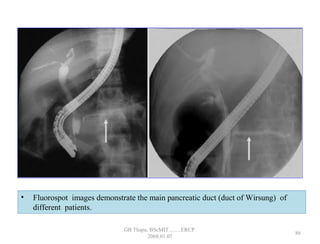

• Fluorospot images demonstrate the main pancreatic duct (duct of Wirsung) of

different patients.